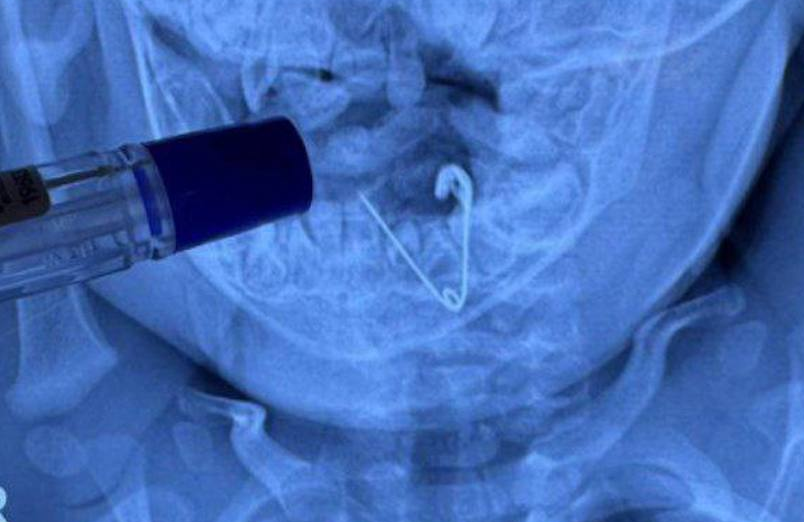

Малыша экстренно доставили в больницу. В результате обследования выяснилось, что в животе у младенца находится раскрытая булавка. К счастью, резать ничего не пришлось, медики сумели вытащить опасный инородный предмет при помощи эндоскопа и щипцов. Сейчас маленький пациент уже полностью здоров.